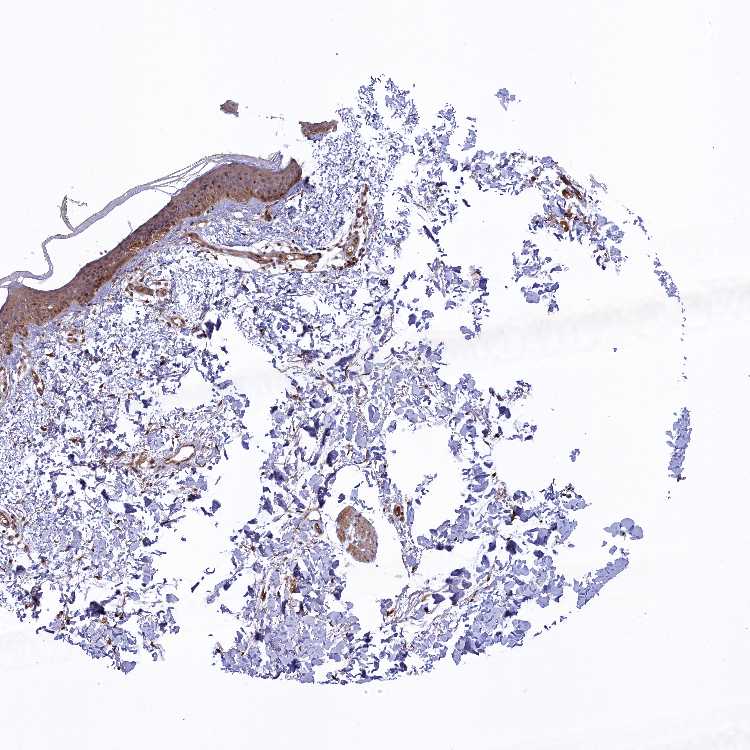

SKIN 1 - Antibody stainingi

Antibody staining in the annotated cell types in the current human tissue is reported as not detected, low, medium, or high, based on conventional immunohistochemistry profiling in selected tissues. This score is based on the combination of the staining intensity and fraction of stained cells.

Each image is clickable and will lead to virtual microscopy that enables deeper exploration of all samples and also displays staining intensity scores, fraction scores and subcellular localization as well as patient and tissue information for each sample.

Antibody HPA043211

Langerhans High

Fibroblasts Medium

Keratinocytes Medium

Melanocytes High

SKIN 2 - Antibody stainingi

Epidermal cells Medium